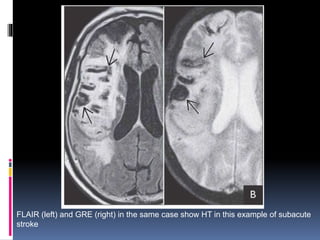

FLAIR (left) and GRE (right) in the same case show HT in this example of subacute

stroke